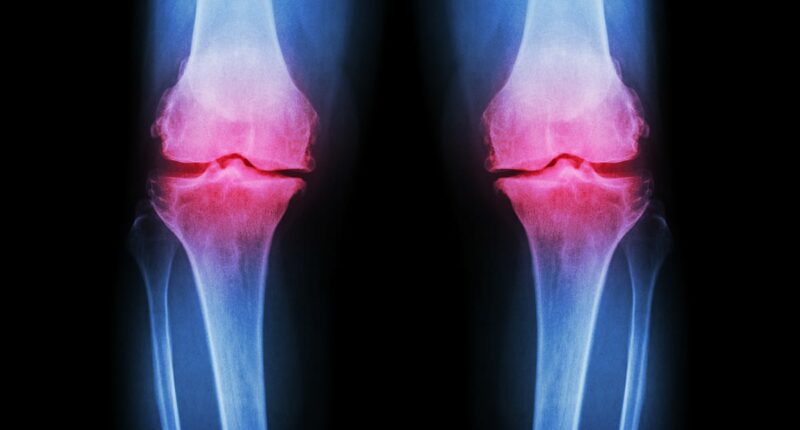

While exercise is widely recognized as one of the most effective defenses against osteoarthritis—a debilitating condition that causes joint pain and stiffness—there is a pressing need to educate the younger demographic about the importance of balanced nutrition and proper resistance training. Without this awareness, they risk sustaining cartilage damage and soft tissue injuries, which are becoming increasingly prevalent in younger patients.

Tim Sinnett, a prominent trauma and orthopaedic consultant, highlights a worrying trend: “We are seeing younger and younger patients presenting with more advanced cartilage damage. The assumption is that these are the results of extreme and intense exercise regimes.” As such, a more informed approach to fitness, incorporating a balance of exercise types and dietary habits, is crucial to safeguarding the health and well-being of future generations.

‘We are seeing younger and younger patients presenting with more advanced cartilage damage, and the presumption there is that they’re picking up more soft tissue injuries around the joint, as a result of more extreme and more intense exercise,’ explained Tim Sinnett, a leading trauma and orthopaedic consultant.

By the age of 70, around half of people will develop arthritis, but some are affected much younger. Osteoarthritis, which affects around 10 million people in the UK, is the most common type of the condition, and is increasingly being diagnosed in the younger generations.

But in osteoarthritis, the protective cartilage on the ends of bones breaks down until the joints are no longer able to fully repair themselves.

A range of factors is thought to cause this increase in cartilage degradation, including genetics, obesity, repeated stress on joints, age, smoking and injury.

Post-traumatic osteoarthritis is related to fractures that extend into a joint such as the ankle, wrist and knee.

These can cause improper healing which alters joint mechanics and leads to cartilage breaking down more rapidly.

Osteoarthritis develops when the cartilage that cushions joints breaks down over time. Cartilage normally acts as a shock absorber, allowing bones to move smoothly.

As it wears away, joints lose this protection and bones eventually rub together, resulting in swelling, tenderness, and grating when moving the affected joints.

The severity of the condition can vary, and usually takes years to develop. Early symptoms such as mild knee or hip pain or stiffness that comes and goes are often dismissed as a sign of needing to exercise more.